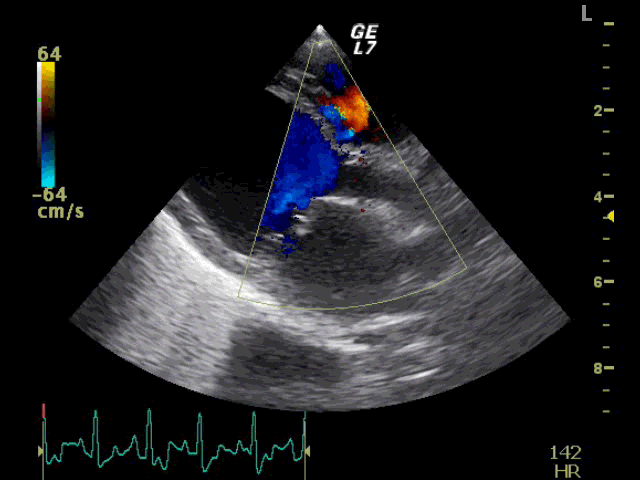

TOP > 内科 > 大動脈弁逆流の動画

循環器科:僧帽弁逆流、三尖弁逆流、大動脈弁逆流の動画